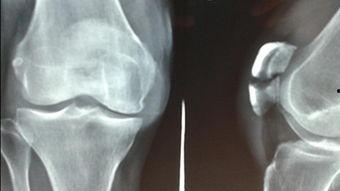

首先,让我们来了解一下什么是骨折。骨折,简单来说,就是骨头断裂了。这种断裂,可能是由于外力撞击,也可能是由于骨质疏松等原因。而骨折的痛苦,可不是一般的大哦!

想象当你突然感到一阵剧痛,骨头像被撕裂了一般,那种感觉,简直无法用言语来形容。而骨折后的恢复过程,更是漫长而痛苦。据数据显示,骨折后,患者需要平均花费6个月的时间来恢复。